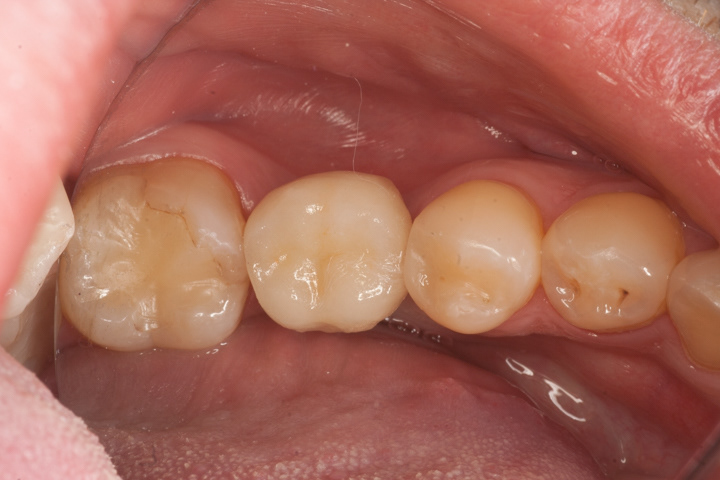

Alternatywą dla mostów są implanty, które pozwalają uzyskać całkowicie nowy ząb bez ingerencji w zęby sąsiednie. Mogą być zatem czyszczone nitką po obu stronach, lepiej prezentują się w strefach estetycznych. Ich wady to wyższa cena, dłuższy czas leczenia i wrażliwość na niedostateczną higienizację. Poniżej zamieszczam kilka przykładów wstawiania zębów za pomocą implantów.

Jest to standardowa procedura wszczepiania implantu i jego odbudowy ze wszystkimi etapami pośrednimi począwszy od usunięcia zęba do cementowanej korony.